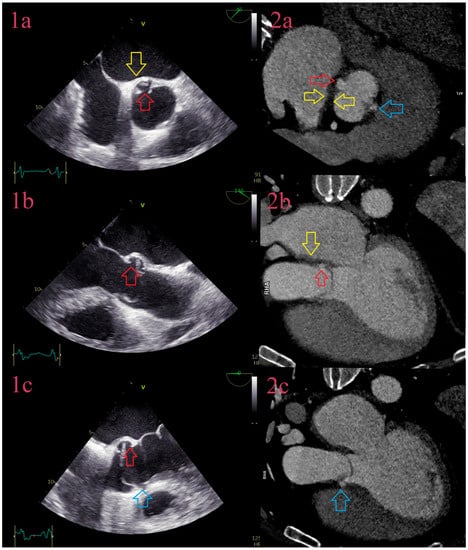

3.3. Vegetations

3.4. Aneurysms

3.5. Perforations

3.6. Abscesses